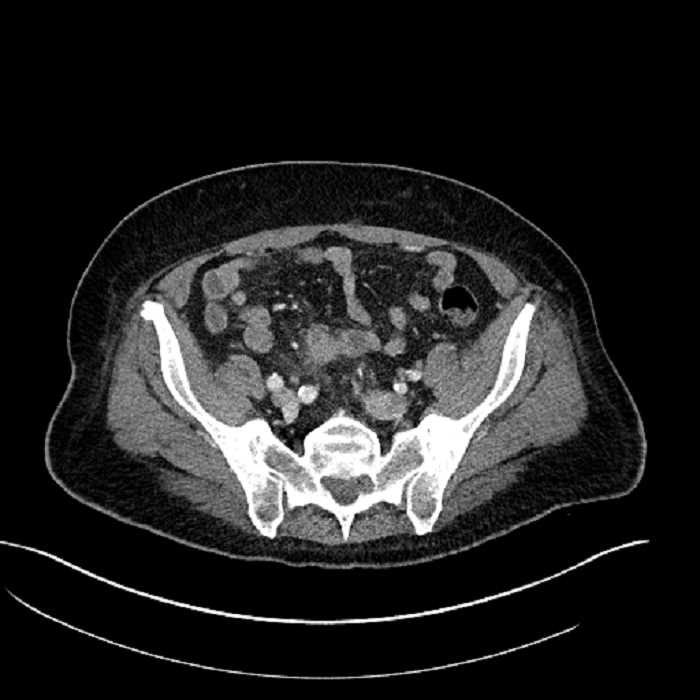

Age: 63

Sex: Male

Indication: Abdominal pain

• Large fluid density structure in hepatic segments 7 and 8 measuring 10 x 7 x 7 cm with internal septation and circumferential ill-defined low density compatible with edema

• Peripherally enhancing subcapsular collections along the anterior margin of the left hepatic lobe measuring 3 x 1 cm and 2 x 1 cm

• Clearly marginated fluid density structure in segment 7 and several other scattered tiny hypodensities, which likely represent cysts

• Mild mural thickening of a segment of the sigmoid colon with adjacent fat stranding and a 1.5 cm fluid and gas collection along the tip of an inflamed diverticulum

• Loss of the normal fat plane between this collection and adjacent loops of small bowel, which demonstrate mural thickening

• High grade stenosis of the left common iliac artery, with the left internal and external iliac arteries remaining patent

• Ankylosis of both sacroiliac joints

• Hepatic abscess

Acute sigmoid diverticulitis complicated by a small contained perforation and a large abscess in the right hepatic lobe. Additional small subcapsular abscesses along the anterior margin of the left hepatic lobe.

Additionally, loss of the normal fat plane between the peridiverticular collection and adjacent thickened loops of small bowel raises the potential for an enterocolonic fistula.

High grade stenosis of the left common iliac artery. The left external and internal iliac arteries are patent.

Hepatic abscess showing the double target sign with low density internally surrounded by a thin inner enhancing rim (red arrow) and ill-defined outer low density rim (yellow arrow). Blue arrow indicates an internal septation. Red arrows: additional smaller subcapsular abscesses. Red arrow: focal contained perforation associated with diverticulitis.